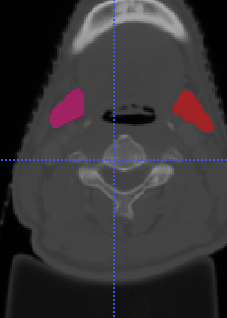

In Chapter 6, we propose an end-to-end, atlas-free 3D convolutional deep learning framework for fast and fully automated whole-volume HaN anatomy segmentation [115]. Our deep learning model, called AnatomyNet, segments OARs from head and neck CT images in an end-to-end fashion, receiving whole-volume HaN CT images as input and generating masks of all OARs of interest in one shot. AnatomyNet is built upon the popular 3D U-net architecture, but extends it in three important ways: 1) a new encoding scheme to allow auto-segmentation on whole-volume CT images instead of local patches or subsets of slices, 2) incorporating 3D squeeze-and-excitation residual blocks in encoding layers for better feature representation, and 3) a new loss function combining Dice scores and focal loss to facilitate the training of the neural model. These features are designed to address two main challenges in deep-learning-based HaN segmentation: a) segmenting small anatomies (i.e., optic chiasm and optic nerves) occupying only a few slices, and b) training with inconsistent data annotations with missing ground truth for some anatomical structures. We collect 261 HaN CT images to train AnatomyNet, and use MICCAI Head and Neck Auto Segmentation Challenge 2015 as a benchmark dataset to evaluate the performance of AnatomyNet. The objective is to segment nine anatomies: brain stem, chiasm, mandible, optic nerve left, optic nerve right, parotid gland left, parotid gland right, submandibular gland left, and submandibular gland right. Compared to previous state-of-the-art results from the MICCAI 2015 competition, AnatomyNet increases Dice similarity coefficient by 3.3% on average. AnatomyNet takes about 0.12 seconds to fully segment a head and neck CT image of dimension , significantly faster than previous methods. In addition, the model is able to process whole-volume CT images and delineate all OARs in one pass, requiring little pre- or post-processing. We demonstrate that our proposed model can improve segmentation accuracy and simplify the auto-segmentation pipeline. These contributions are released as an open-source software package called AnatomyNet, which is publicly available555https://github.com/wentaozhu/AnatomyNet-for-anatomical-segmentation. Portions of this chapter were published as part of [115].